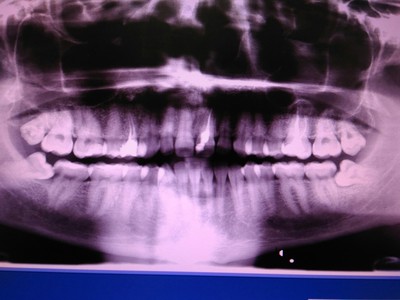

А для того, что ортопантомография (ОПТГ, обзорный или панорамный снимок зубов), является плоскостным, а значит происходит наложение каждой детали снимка послойно друг на друга. Следовательно, рассмотреть объект исследования, в частности, область зуба мудрости, расположенного рядом нижнечелюстного нерва, во всех плоскостях, под иным углом или другой проекции невозможно. КЛКТ (Конусно-лучевая компьютерная томография), напротив дает нам такую возможность.